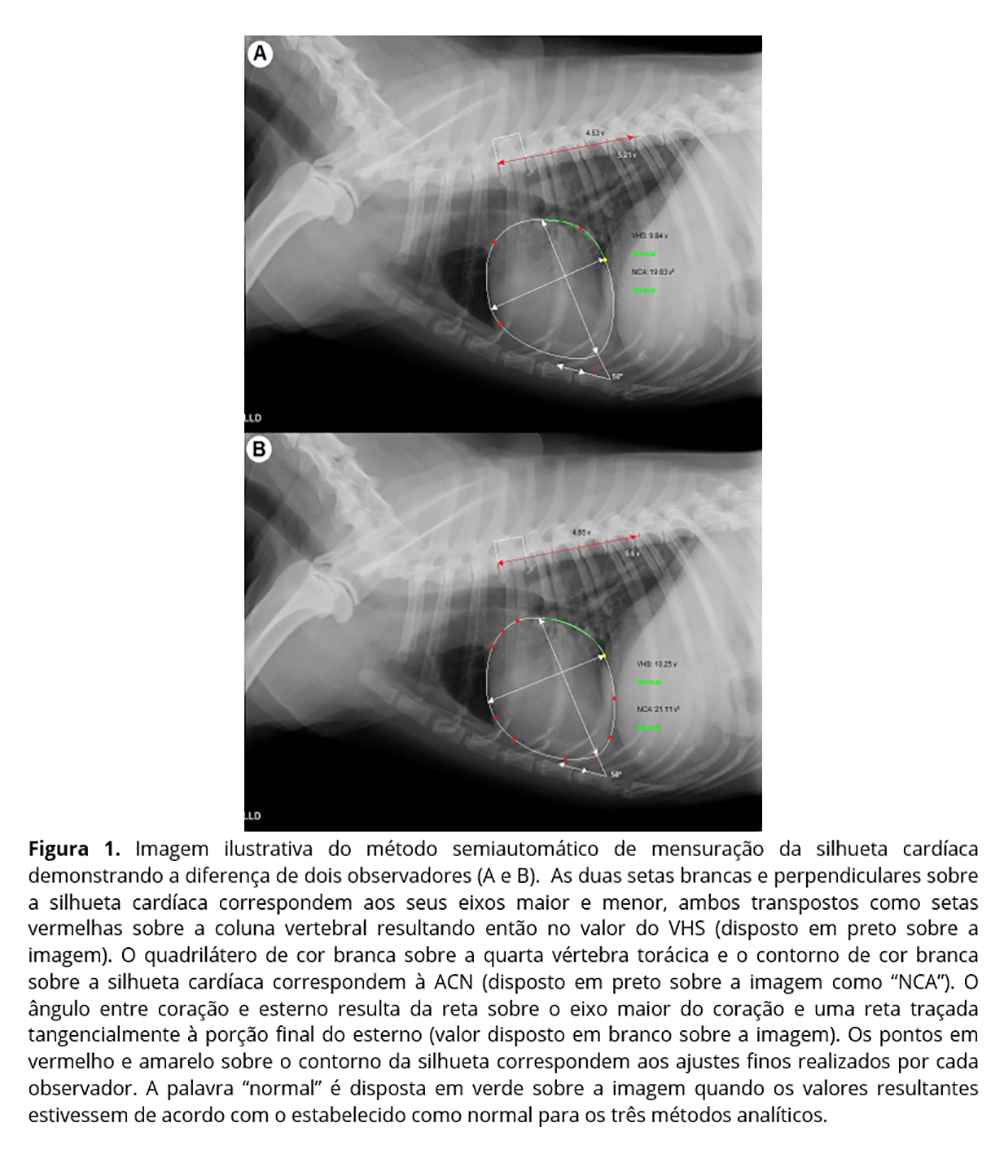

O observador B2 foi o único a apresentar repetibilidade e reprodutibilidade para todos os parâmetros. Experiente em radiodiagnóstico, este observador possuía familiaridade prévia com o sistema de mensuração em questão, o que poderia explicar tanto a falta de repetibilidade da ACN para os observadores sem experiência em radiodiagnóstico (maior dificuldade em estabelecer os limites de estruturas intratorácicas) quanto para o observador B1, que também possuía experiência em radiodiagnóstico, porém não estava familiarizado com o software. A familiaridade com o software junto à experiência em radiodiagnóstico implicaria em um melhor aproveitamento das ferramentas disponíveis para realizar ajustes finos das medidas pré-determinadas pelo programa (em especial para a ACN), conferindo maior consistência às mensurações (figura 1).

Visando diminuir a subjetividade do método empírico, vários métodos de mensuração foram propostos(8,15-19). A área cardíaca normalizada (ACN) e o vertebral heart score (VHS) são alguns destes métodos. O VHS foi um método proposto por Buchanan e Bucheler(8) no qual duas retas perpendiculares são traçadas sobre a silhueta cardíaca e posteriormente transpostas sobre a coluna vertebral do paciente a partir da quarta vértebra torácica, e o valor é dado em unidades de vértebra. Já a ACN, estabelecida por Fonseca Pinto(19), consiste na razão entre a área interna ao contorno da silhueta cardíaca e a área de um quadrado de base correspondente a um quinto da distância entre a quarta e oitava vértebras torácicas, sendo o valor dado como unidades de vértebra ao quadrado. Ambas são ferramentas úteis na prática radiológica, sendo o VHS considerado o mais indicado como método de triagem das cardiomegalias(20), tendo alguns trabalhos já explorado sua variação entre observadores(21-23).